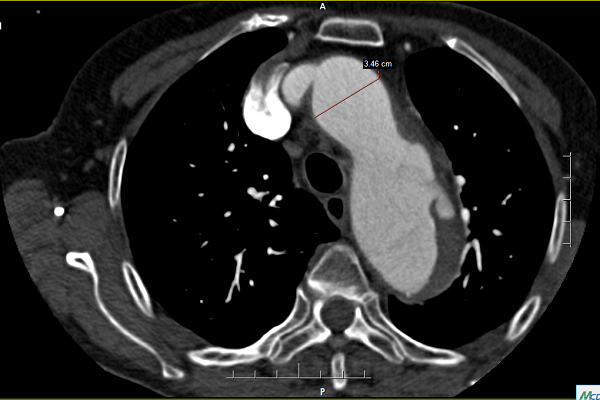

出现此种症状时需要完成的检查包括常规的心电图、心肌酶、凝血功能,上述检查主要用于鉴别诊断,主要与心肌梗塞、肺动脉栓塞相鉴别。明确诊断需要行胸腹主动脉的CTA检查(CT血管成像)。确诊之后需要及时转入血管外科,首先要做的就是镇痛、控制血压和心率,然后依据CTA结果确定患者病变分型,依据分型制定手术方案。

目前有两种分型方式(如上图所示),临床中更常用的是Stanford分型,B型基本可通过覆膜支架的植入完成微创治疗,而A型往往提示病变更复杂,有些患者需要行传统开刀手术,但随着腔内器械及手术技术的提高和创新,目前大多A型病变的患者可通过烟囱、开窗或者分支支架的方式完成腔内治疗,极大降低了手术创伤和风险,提高了患者生存率。